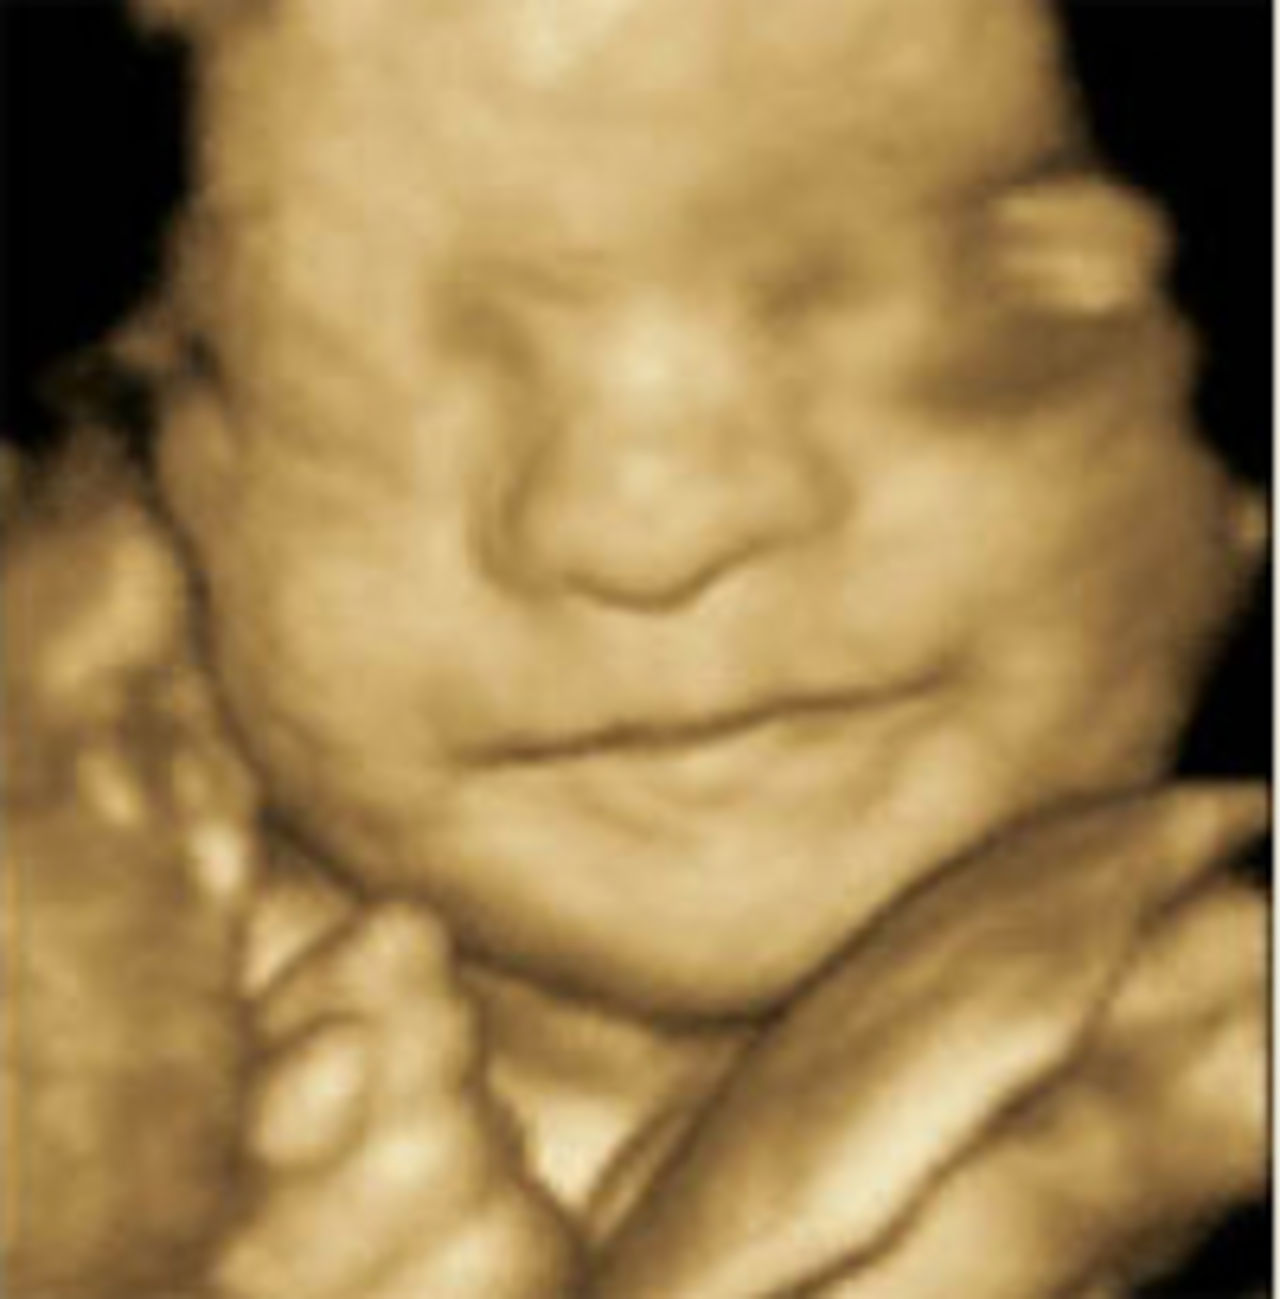

4D-ultraljudet är här! Nu kan du se ditt barn röra sig i magen. 4D-ultraljudet är här! Grattis alla gravida! Nu öppnar den första svenska ultraljudskliniken som erbjuder ultraljud med 4D-teknik. Tidigare har man enbart kunnat se foster på traditionella svartvita 2D-bilder. Och hur mycket man än tyckte att man hade världens finaste bebis i magen när man tittade på den där lilla bilden så måste jag säga att det här är snäppet coolare. Hos Tittut använder man den allra senaste tekniken inom ultraljud. Det innebär att man kan se en verklig och detaljerad bild av barnet och även tydliga rörelser som är väldigt svåra att se och identifiera med klassisk 2D-scanning.

Vem skulle inte vilja se hur den lilla bebisen därinne gäspar, sträcker ut tungan, ler, sväljer, blinkar och rör på fingrarna.